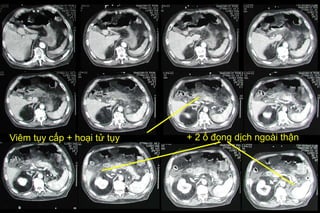

Chẩn đoán hình ảnh Viêm tụy cấp: Hoại tử

Viêm tụy cấp + hoại tử tụy + 2 ổ đọng dịch ngoài thận